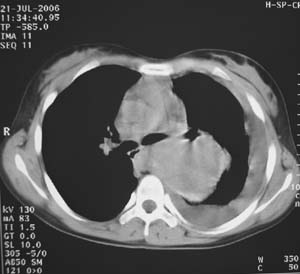

女性,17岁,一年前因股骨病变截肢,现胸憋。

左肺巨大肿块,内散在斑点状高密度骨化影,右肺见多发结节灶,双侧胸膜局限性增厚。有骨肉瘤病史,支持骨肉瘤手术后转移。